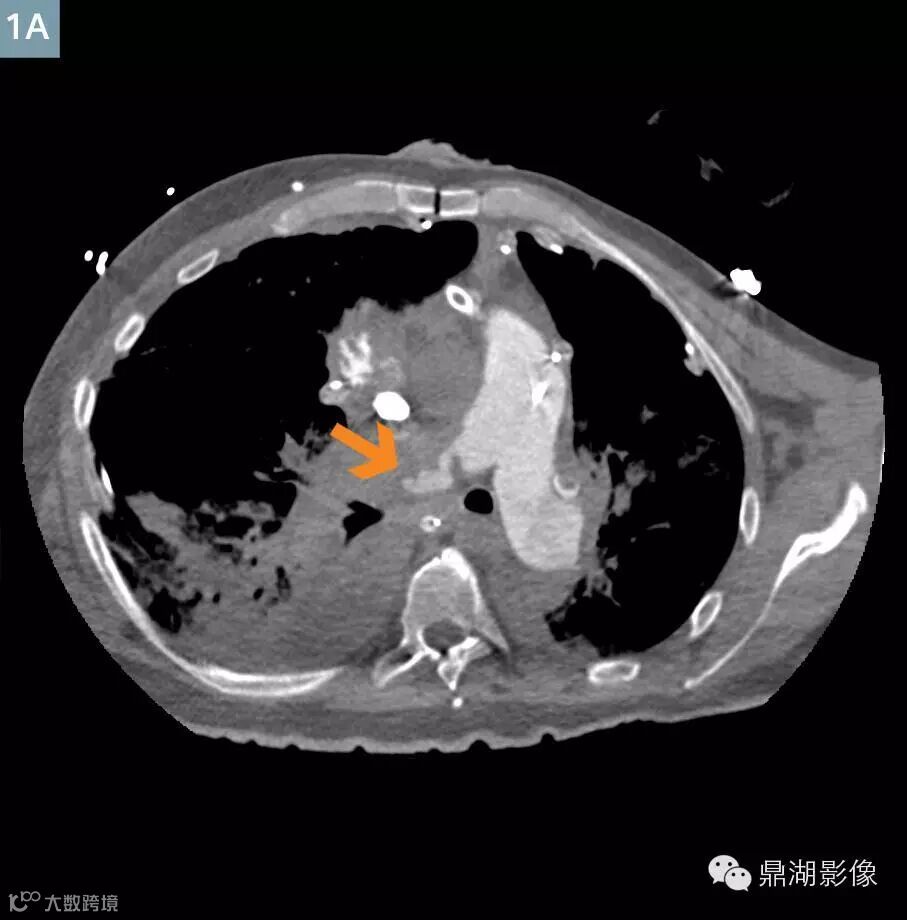

Axial contrast-enhanced (Fig. 1A) and VRT (Fig. 1B) image at the level of the main pulmonary artery: There are irregular filling defects (arrow) in the occluded right main pulmonary artery consistent with thrombosis.

肺动脉CTA显示新的多发性肺栓塞和右动脉完全闭塞(图1)。左下叶肺动脉和静脉灌注一直持续(图3)。存在广泛右肺动脉梗塞(图2)。上腔静脉,右心房,右心室充满造影剂,造影剂回流进入肝静脉和下腔静脉(图5A)。主肺动脉CT值衰减大于250亨氏单位,这可以让医生确定扫描的诊断质量。ECMO系统和主动脉的分支未显影,体现了良好的团注时间(图4)。